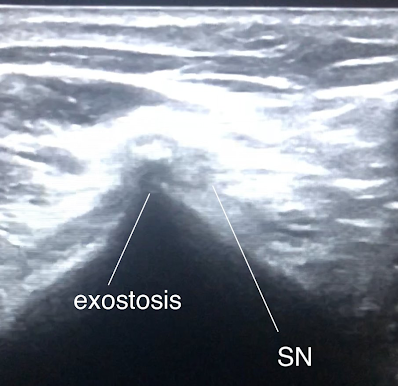

Bony exostoses (benign outgrowth)

Surprisingly common around the knee and the majority are asymptomatic and go unnoticed – but if in the wrong place or large enough, they can cause compressive mischief!

Patients may have a hard block on functional ROM (e.g. squat, kneeling which insidiously progresses).

They can cause local irritation of soft tissues (e.g. hamstring muscle / tendon) or may have progressive neural compressive symptoms.

In the below clip, we can see a large posterior femoral exostosis causing sciatic nerve irritation on dynamic hamstring contraction, triggering distal posterior thigh pain into lateral knee and lower leg.

Treatment? Excise it! But, make sure it’s the cause – it’s prudent to get nerve conduction studies and MRI lumbar spine.